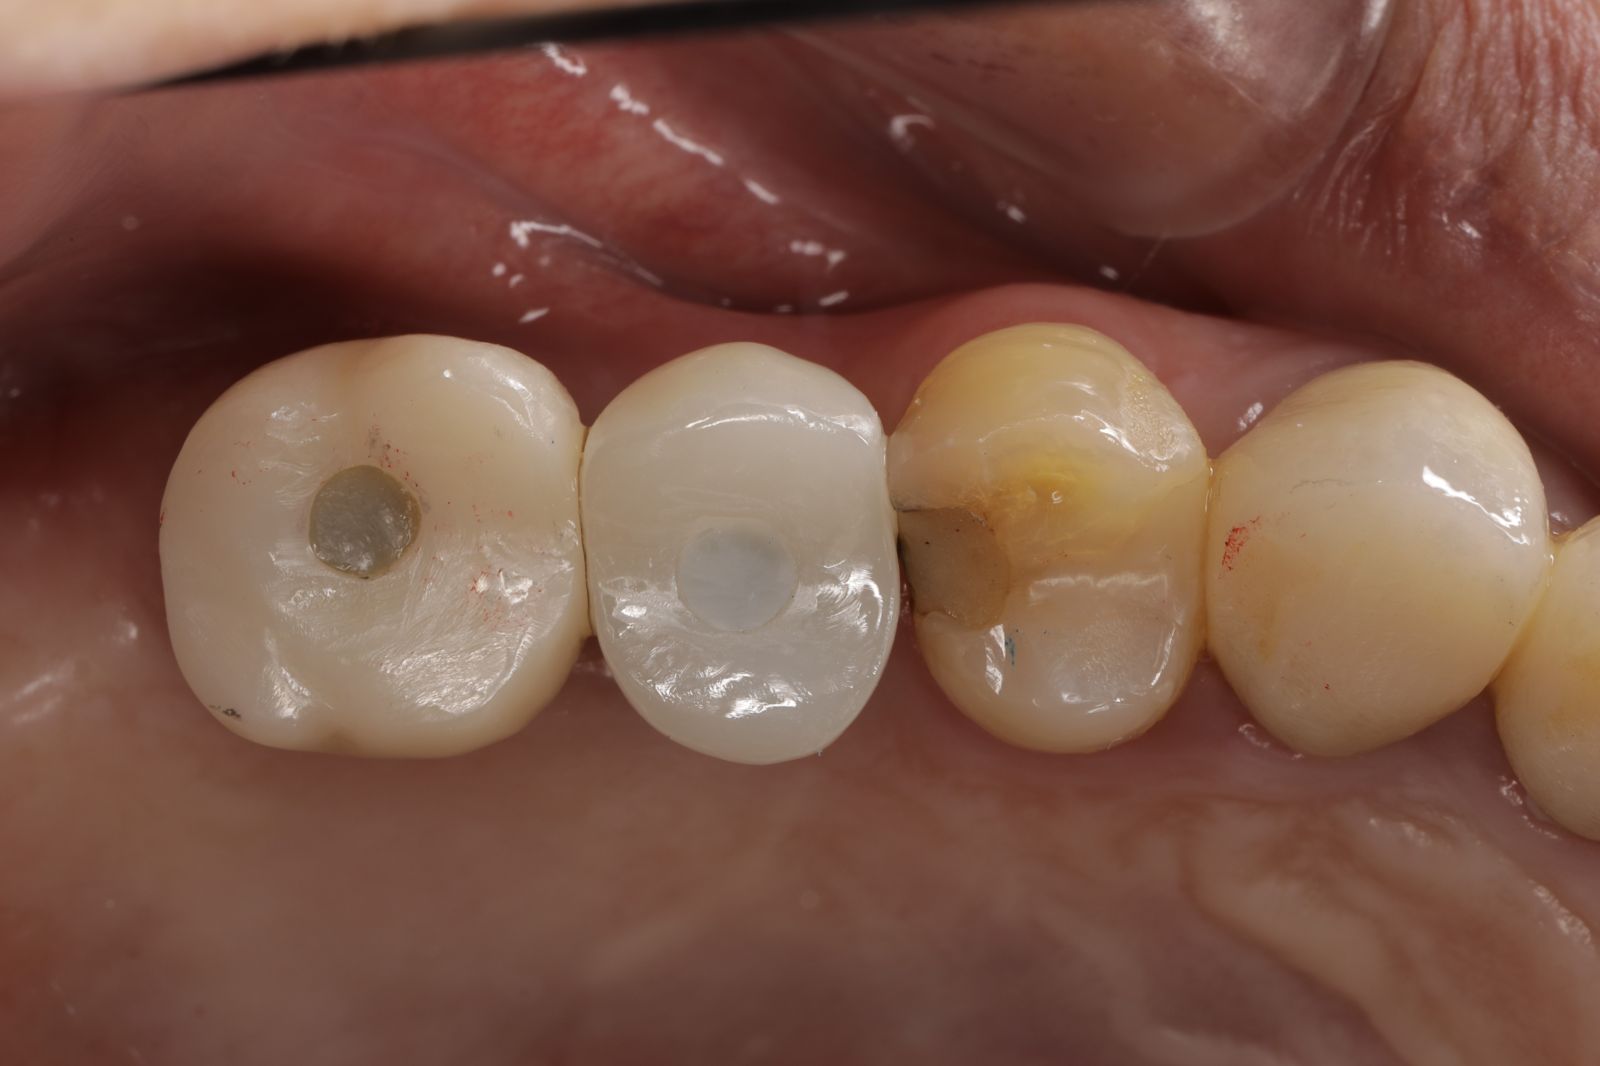

【 案 例 三 】

- 手術過程,在植入植體前先用導板定位,確認植牙位置及角度。使用導板讓傷口範圍縮小。

- 手術後傷口小無需縫合,也不用再來拆線,幾乎不會腫脹出血,術後恢復期舒適快速!

- 待3.4個月後裝上全陶瓷牙冠完成植牙療程。整個療程過程輕鬆。